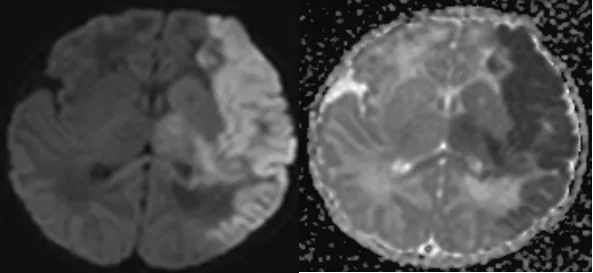

7月11日,黄陂区人民医院放射影像科二区(磁共振室)医师到新生儿与危重症医学科开展“磁共振临床读片会”,此次读片会主题为“新生儿颅脑病变磁共振检查相关知识”。

7月10日,新生儿科刚出生一天的患儿因“阵发性青紫半天”行磁共振检查,诊断该患儿为左侧大脑中动脉供血区急性大面积脑梗死,磁共振医生第一时间报告临床,及时准确的为临床提供影像诊断意见,为新生儿的救治提供有力的支持。